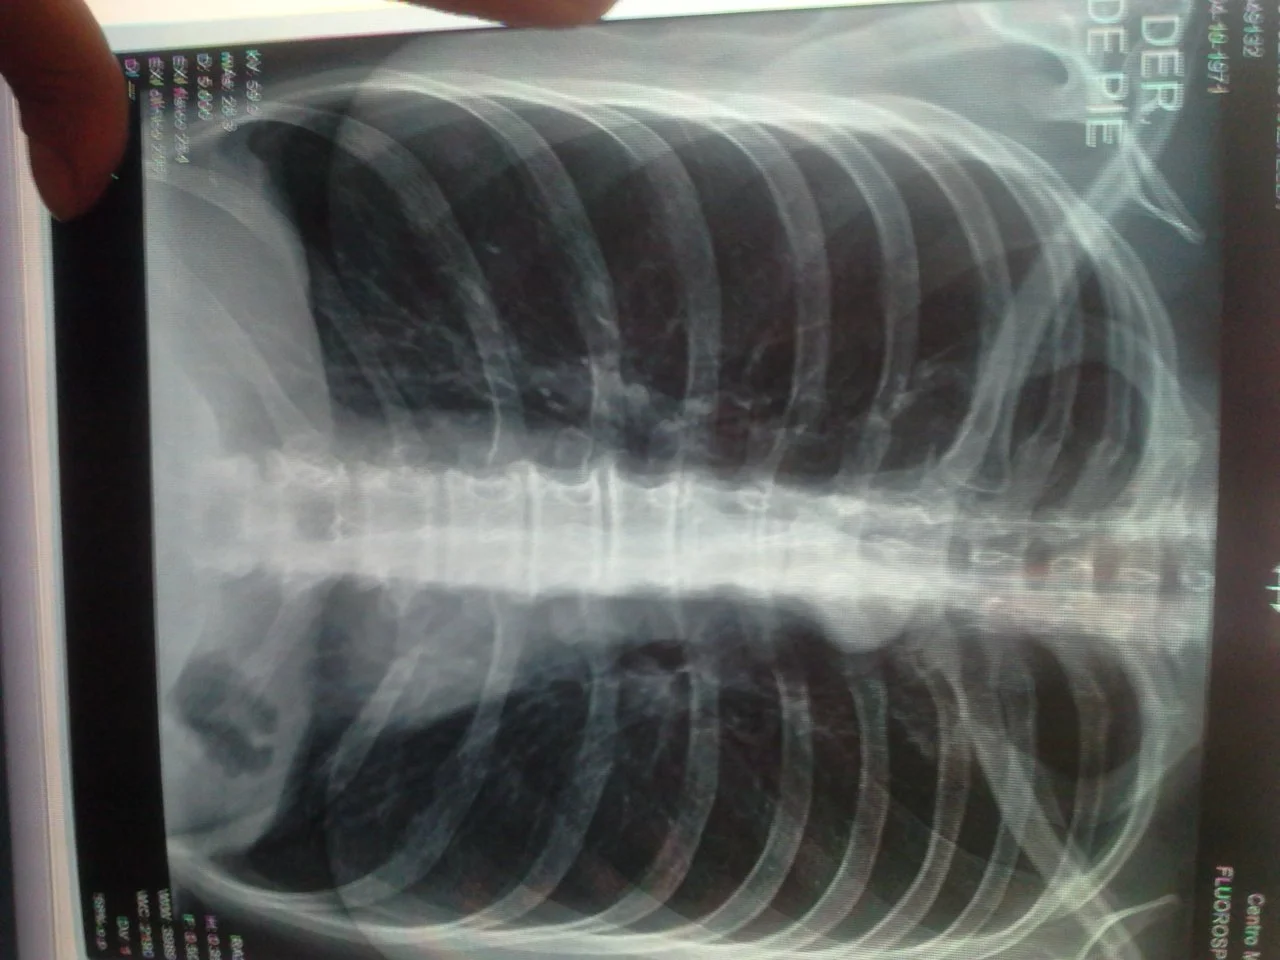

Добрый день! роходила обследование по подготовке к операции по удалению геморроя и вот такой снимок. Живу в испаноязычной стране и не поняла ни диагноз, ни термины. Поняла только, что через пол года мне светит кислородный баллон. Так все плохо? 47 лет, курю 30.

хобл они ставят под вопросом.все же надеюсь, что заглянет в тему врач.

Вроде нет ничего об эмфиземе, а лишь наблюдается легкое изменение (una ligera), расширение пространств бронхиол.

condensacion parenquimatosa: ателектаз, наверное? Нет.

И далее написано, вроде, что нужны и другие анализы для следующего осмотра.

Снимок, никто не лечит.Какие у вас симптомы:одышка,быстрая утомляемостькашель с мокротой?.Другое исследование:общий крови,ЭКГ?КТ или бронхоскопия более информативна.Заключение местами не вижу что написано